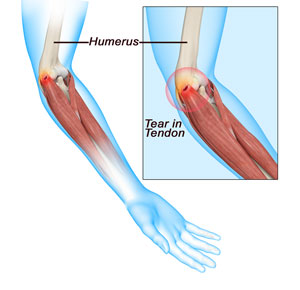

The elbow is a joint made up of three bones: the upper arm bone, the humerus, and the two forearm bones, the radius and ulna. The lower end of the humerus has bony bumps called epicondyles that serve as sites of attachment for major tendons and muscles that help in arm movement. The bump on the outside of the elbow is called the lateral epicondyle. It helps in the attachment of the tendons and muscles that help extend your fingers and wrist.

Tennis elbow is a common name for the elbow condition lateral epicondylitis. It is an overuse injury that causes inflammation and microtears of the tendons that attach to the lateral epicondyle.

Tennis elbow is usually caused by overuse of the forearm muscles but may also be caused by direct trauma such as with a fall, car accident or work injury.